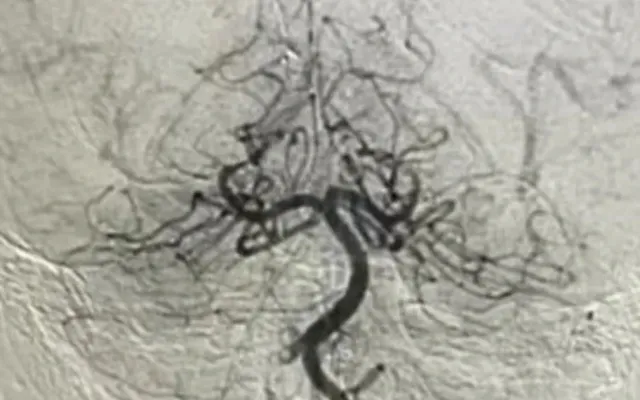

Bệnh viện lập tức hội chẩn liên chuyên khoa và chỉ định chụp mạch máu não số hóa xóa nền (DSA) để đánh giá chính xác tình trạng tắc mạch. Sau đó, bệnh nhi được can thiệp nội mạch cấp cứu. Các bác sĩ luồn ống thông qua động mạch đùi, tiếp cận vị trí tắc ở động mạch đốt sống, sử dụng thuốc tiêu sợi huyết tại chỗ kết hợp dụng cụ chuyên biệt để lấy huyết khối, tái thông dòng máu lên não.

Sau can thiệp, bé tỉnh táo, tiếp xúc tốt, các chỉ số sinh tồn ổn định, mạch máu được tái thông hoàn toàn và tưới máu não cải thiện rõ. Trẻ được chuyển về khoa Hồi sức ngoại để theo dõi và phục hồi chức năng. Chỉ sau một tuần, bệnh nhi đã vận động gần như bình thường.